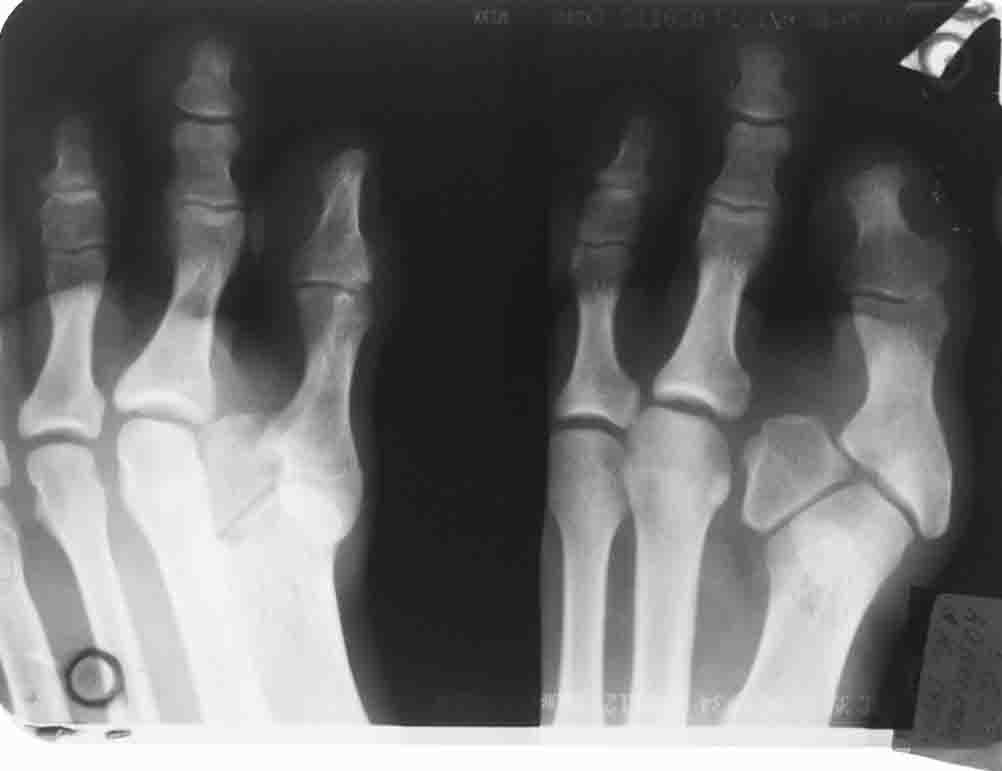

Укорочение 1 п. Смещение о/ф 1 п кнаружи и к тылу. Пассивные активные движения 1 п в полномобъеме. На рентгенограмме определяется аномальная кость.

Происхождение такого состояния можно теоретически объяснить либо врожденной аномалией оссификации проксимальной фаланги большого пальца (два ядра)-об этом признаться я не слышал и не приходилось встречать в литературе, либо (что выглядит наиболее практичным) - это травма зоны роста в детстве по типу Salter-Harris 1 или 2 типа, что и привело к нарушению нормального роста первого пальца и деформации 1 плюсне-фалангового сустава. Не думаю, что пункциями и АБ можно вылечить сформировавшийся свищ, скорее более успешной тактикой в такой ситуации будет хирургическое иссечение свищевого хода после предварительного введения метиленой синьки. (все прокрашенные ткани иссекаются).

1. Судя по снимкам, рентгенограммам и клинике - это хр.остеомиелит ( и хр.артрит) одной из сочленяющихся костей 1ПФС, (я бы уточнил источник), свищевая форма, на фоне аномального развития 1 ПФС (врожденного или приобретенного - сейчас это уже не важно).